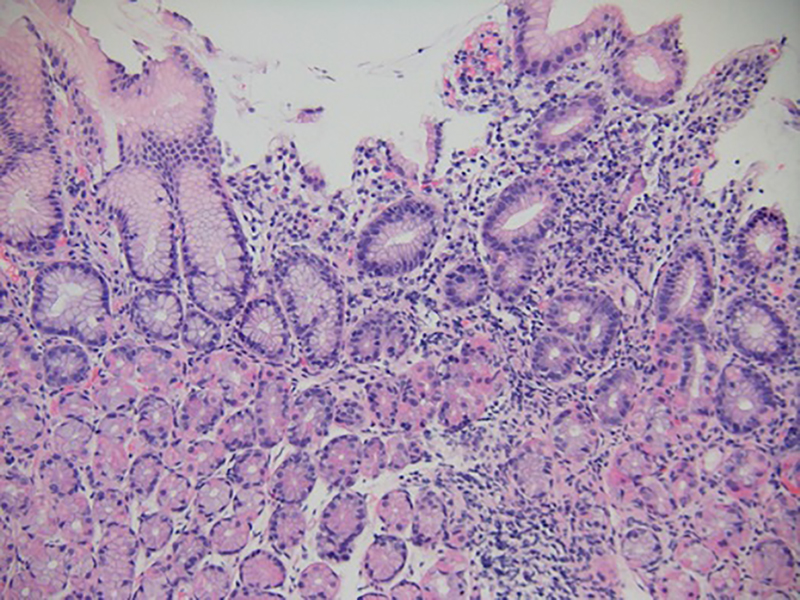

The patient underwent GI tract esophagogastroduodenoscopy 24 hours after admission. Results revealed severely inflamed, diffusely erythematous mucosa in the stomach (Figure 1A) and diffusely erythematous, congested mucosa with overlying exudate in the duodenum (Figure 1B). Gastric biopsy specimens demonstrated focally active gastritis without granuloma formation (Figure 2). Giemsa stain results were negative for Helicobacter pylori. Duodenal biopsy specimens showed active duodenitis with acute cryptitis, crypt abscess formation, and mild villous blunting without granulomas or viral inclusions (Figure 3). Results of colonoscopy with examination of the terminal ileum revealed mild colonic inflammation, extending from the rectum to the mid-ascending colon (Figure 4A). The most severe condition appeared to be in a rectosigmoid distribution. The proximal ascending colon and cecum appeared to be spared. The ileal mucosa appeared erythematous and edematous, with overlying exudate (Figure 4B). Biopsy specimens of the rectum, the sigmoid, and descending, transverse, and proximal ascending colon demonstrated mild active colitis with acute cryptitis, crypt abscesses, and neutrophils within the lamina propria (Figure 5). Biopsy specimens of the distal ileum showed moderate active ileitis with acute cryptitis, crypt abscesses, and focal architectural distortion (Figure 6).

Gastric biopsy specimen taken 2 weeks after ipilimumab administration demonstrated focally active gastritis without granuloma formation (hematoxylin-eosin, original magnification ×100).

Duodenal biopsy specimens taken 2 weeks after ipilimumab administration demonstrated active duodenitis with acute cryptitis, crypt abscess formation, and mild villous blunting (hematoxylin-eosin, original magnification ×100).